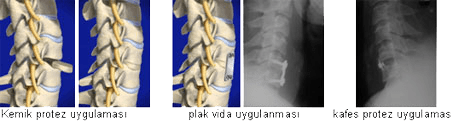

Boyun Fıtığı Cerrahisi

Omurilik ve sinir dokusuna olan basıyı kaldırmak cerrahi tedavinin amacıdır. Endikasyonu doğru olan ve mikrocerrahi teknik ile yapılan cerrahide hastanın, ağrısının geçmesi, uyuşma-kuvvetsizlik gibi bulgulardan kurtulması sağlanır. Uygun zamanda ve tecrübeli ellerde yapılan bu girişimler çok iyi sonuç verir. Bu gün için kullanılan yegane yöntem servikal mikrodiskektomidir. Bazı hastalarda, mikrodiskektomiyle beraber, çıkartılan kıkırdağın yerine sentetik protezlerde uygulanır. Servikal mikrodiskektominin avantajları:

Genel anestezi altında ameliyat, boynun ön yüzü, tercihen sağ taraftan uygulanır. Omurga ön yüzüne varan cerrah, skopi kontrolüyle istenilen omurga mesafesine ulaşır. Bu andan itibaren mikroskop kullanarak iki omurga arasındaki fıtıklaşan yapıyı temizlemeye başlar ve sinire veya omuriliğe bası yapan fıtık kaldırılır. Bu işlemi takiben protez greft kullanılır. Omurgada kireçlenme yapmış boyun fıtıklarında füzyon dediğimiz protez uygulamasının yapılması gerekir. 45 yasin altindaki hastalarda ileride füzyon dedigimiz ameliyatin kireçlenmeye neden olmamasi için boyun protezi uygulamasi gerekir.